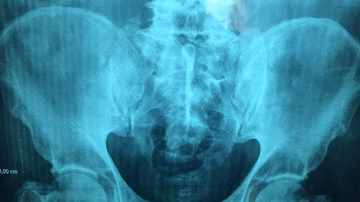

Uhodan posao na crnom tržištu: Prevarili Nepalce da prodaju svoje bubrege, rekli da će im izrasti novi Svijet | 1. tra. | 0